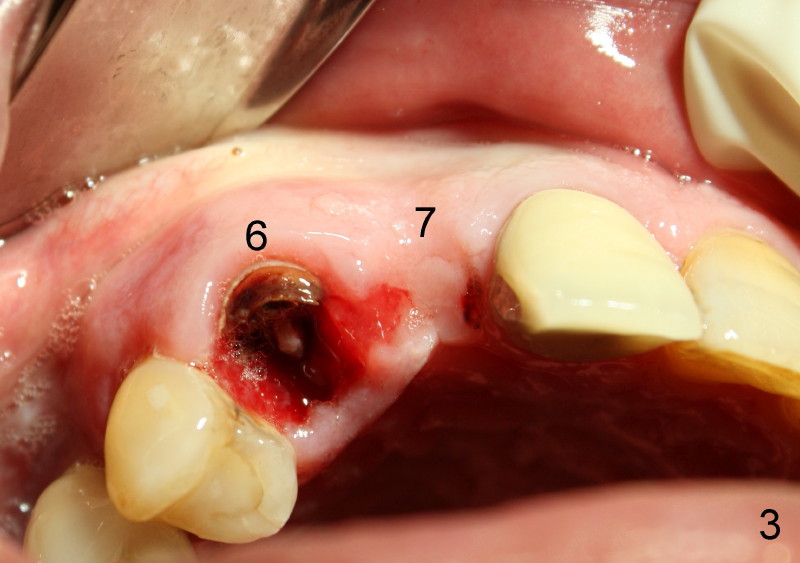

A 73-year-old man feels that upper right bridge is loose. There is subgingival caries (*) under one of its retainers (#6 in Fig.1). CBCT shows that bone volume is sufficient for immediate implant at #6 (Fig.2). When the bridge is sectioned between the pontic #7 and retainer #8, the pontic #7 and retainer #6 complex falls out by themselves. The tooth #6 is deemed nonsalvageable (albeit vital); the labial plate of #7 is atrophic (Fig.3).

Immediately after atraumatic extraction of #6 residual root, the socket is irrigated with normal saline and Chlorhexidine. There is no granulation tissue in the apical area. The root stump is 6 mm mesiodistally and 8.5 mm labiopalatally. Tatum 2 mm pilot drill is used with copious irrigation to penetrate the palatal plate of the socket (as shown by arrow in Fig.2) at the depth of 20 mm from gingival margin. Bicon reamers (cylindrical, from 2.5 mm to 4.0 mm in a sequential order) are used (with 400:1 reduction) for osteotomy without irrigation. Autogenous bone graft is collected to fill the gap between implant and socket. Fig.4 shows 3.0 mm reamer in place (20 mm from the gingival margin). Finally Tatum tapered implant 6x20 mm is torqued in with primary stability (Fig.5: I). There is no gap between the implant and the socket except palatally, where the bone graft is inserted. Two release incisions are placed palatally. The flap is raised. The periosteum is scored at the base. The palatal flap is advanced labially to close the palatal gap with 4-0 chromic gut suture.